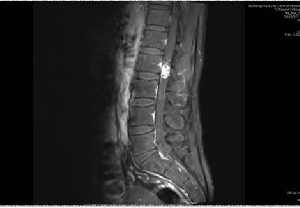

我院神經外科顯微鏡下成功切除椎管內腫瘤1例

日前,神經外二科成功為一名腰2椎管內占位性病變患者實施了顯微鏡下椎管內病變切除術,術后患者癥狀完全改善。患者李某,男,40歲,因“右下肢疼痛、麻木8年余,伴腰